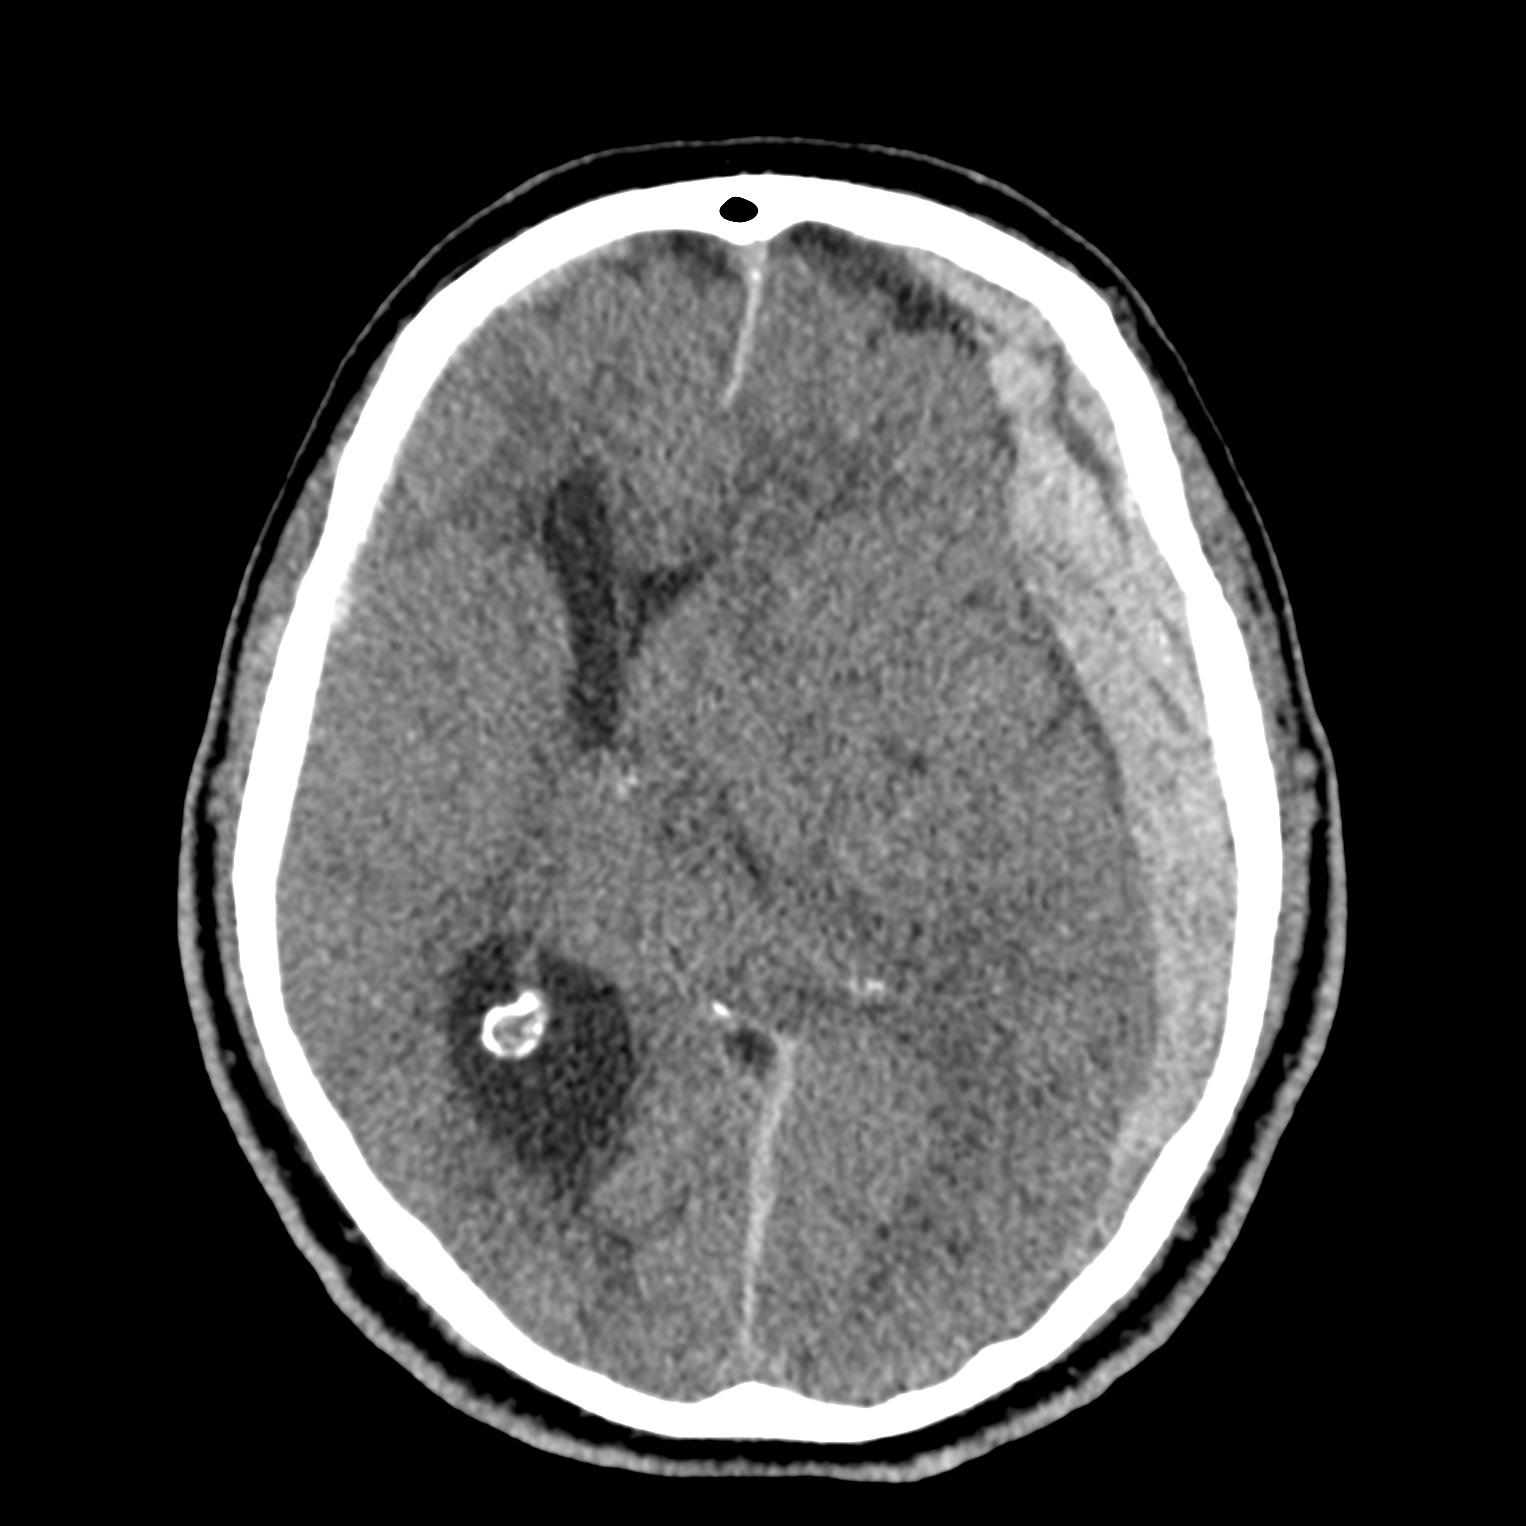

ちなみに画像診断とは、CTやMRIなどの画像を見て、正常か異常か、異常であればそれが何なのかを診断する仕事です。

Case courtesy of Andrew Dixon, Radiopaedia.org. From the case rID: 32383

医療従事者でなければ何のメリットも無いかもしれないのですが、実際の画像を自分でスクロールしながら学ぶことができるというのは、ものすごく大きなことだと思います。

さらに症例の解説を付け加えたら、読影能力アップのための強力なツールになるのではないかと期待しています。